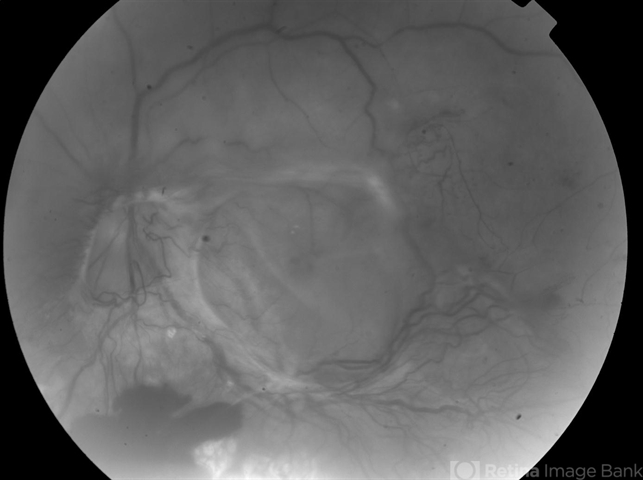

- Diabetic TRD

- diabetic traction detachment, tractional retinal detachment

- Poorly controlled DM missed many appointments due to CVA came in with complaint of floaters; initial red free; CF.